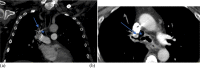

Bronchopulmonary arterial fistula consists of an abnormal connection between the bronchus and the vascular tree and is a rare but serious complication associated with a variety of lung interventions. We present a case of a 61-year-old female with a history of metastatic breast cancer treated with lumpectomy and radiation 20 years prior, who was found to have a fistula between the right pulmonary artery and the right mainstem bronchus. Our patient was treated endovascularly with coil embolization in the setting of massive hemoptysis flooding the trachea, which was successful in controlling the acute bleed, although care was withdrawn in the following days following a discussion with the family given the presence of advanced metastatic disease. This case illustrates the use of endovascular techniques to treat an actively bleeding bronchopulmonary arterial fistulae, including a review of the existing literature regarding the optimal endovascular management strategy. Although our patient did not achieve the best outcome, endovascular intervention with stent-placement or embolization can serve to temporarily halt blood flow through the fistula, stabilizing the patient and allowing for more radical therapy after improvement.